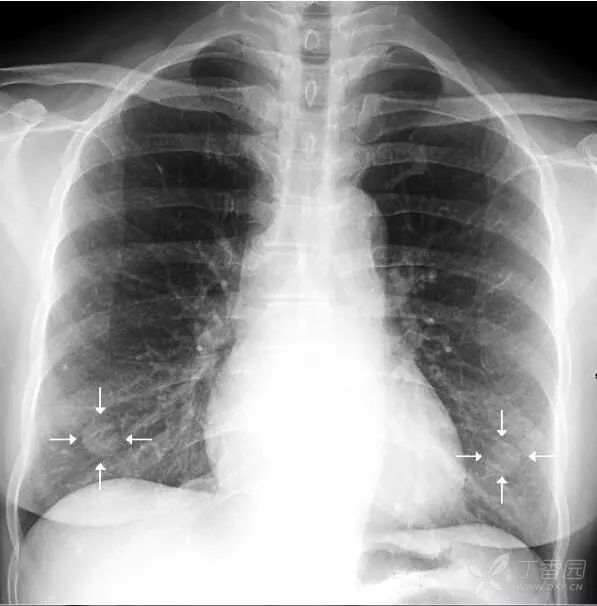

乳 头 乳头有可能会在正位胸片的两肺下野形成直径约1cm的小圆形投影,年龄偏大的妇女更容易出现这种情况。

上图双侧乳头投影(白色箭头)。位于第六前肋水平,两侧比较对称的小圆形阴影。

乳头影须和肺内小结节病灶鉴别,方法是:①双侧乳头的投影的位置通常相对比较固定,多位于两肺下野第5、6前肋处附近。②其位置和大小往往两侧比较对称。如果不易和肺内病灶区别,透视下转动患者体位即可与肺野分开,或采取进一步检查的措施。